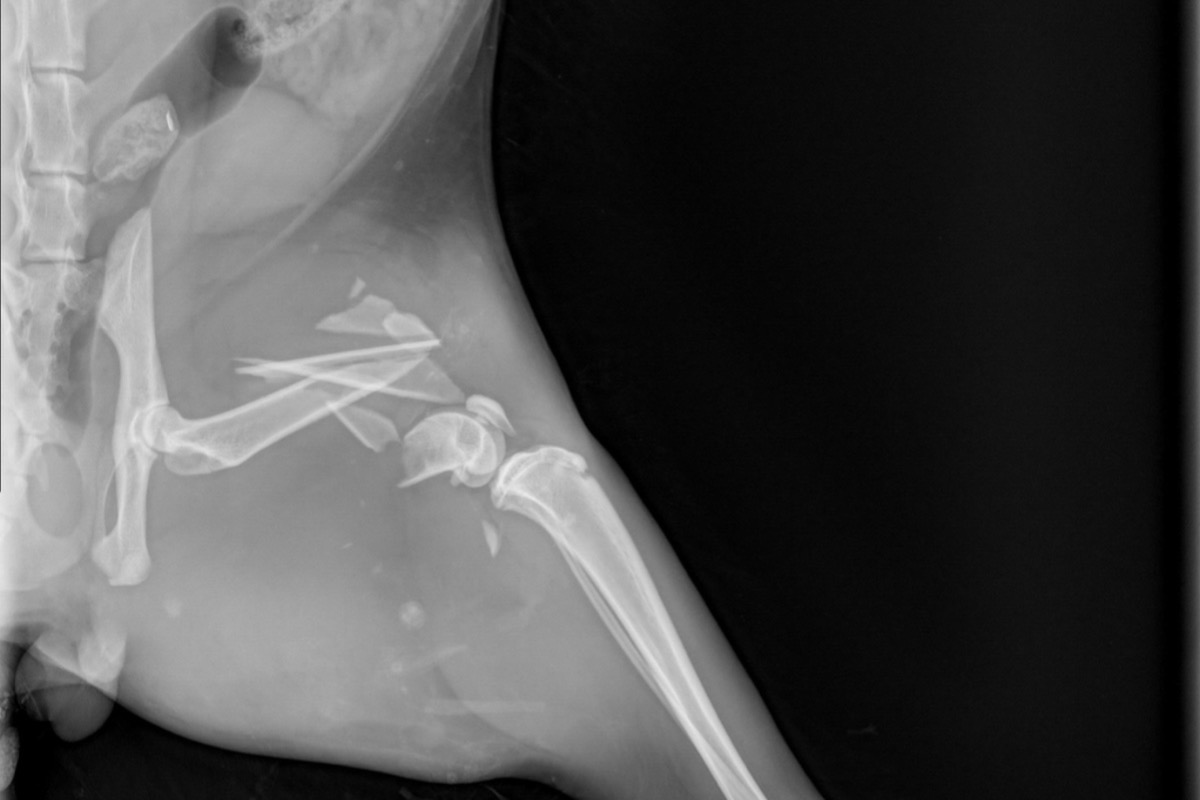

He had been hit by a car. Kitty was almost lifeless. his breath was shallow and deteriorating, his eyes were rolling while his left hind leg was dangling. I ran to my husband (who was giving our 19 month old twins a bath) we stealthy packed up the car and drove to the closest veterinarian hospital. The doctor sedated him to get x-rays and to relive the pain. After the X-rays his vitals were taken. His temperature had dropped so severely the vet urgently wrapped him up in heating blankets and hooked him up to fluids. Doc fed him some vitamins and glucose through the IV to keep him going. The radiography showed no visible signs of internal bleeding but the blood test told a different story. Although he wasn't bleeding internally, the diagnostic test showed that his liver and kidneys were struggling to preform from the impact of the car, not catastrophically enough for emergency surgery but enough to cause concern. He hasn't been able to urinate since and we've been taking him into the vet to relieve his bladder while we await surgery.

As for the X-ray results, we were informed that his femur had shattered into 7 pieces and that the trauma was too great to save his leg. Plating the leg would consist of multiple surgeries with subsequent physical therapy for months and even then there was no guarantee that he would actually be able to use the leg again. After consulting with one another, the orthopedic surgeons agreed that amputation would be the best bet and the most cost effective. Still a whopping 6,000 for the amputation. This doesn't include the overnight care, medication, check ups, or any other variable that may come into affect. This is on top of the 2,000 we have already spent just to diagnose the problem. Kitty is due to get his surgery Tuesday March 31st, one week after this tragic accident.